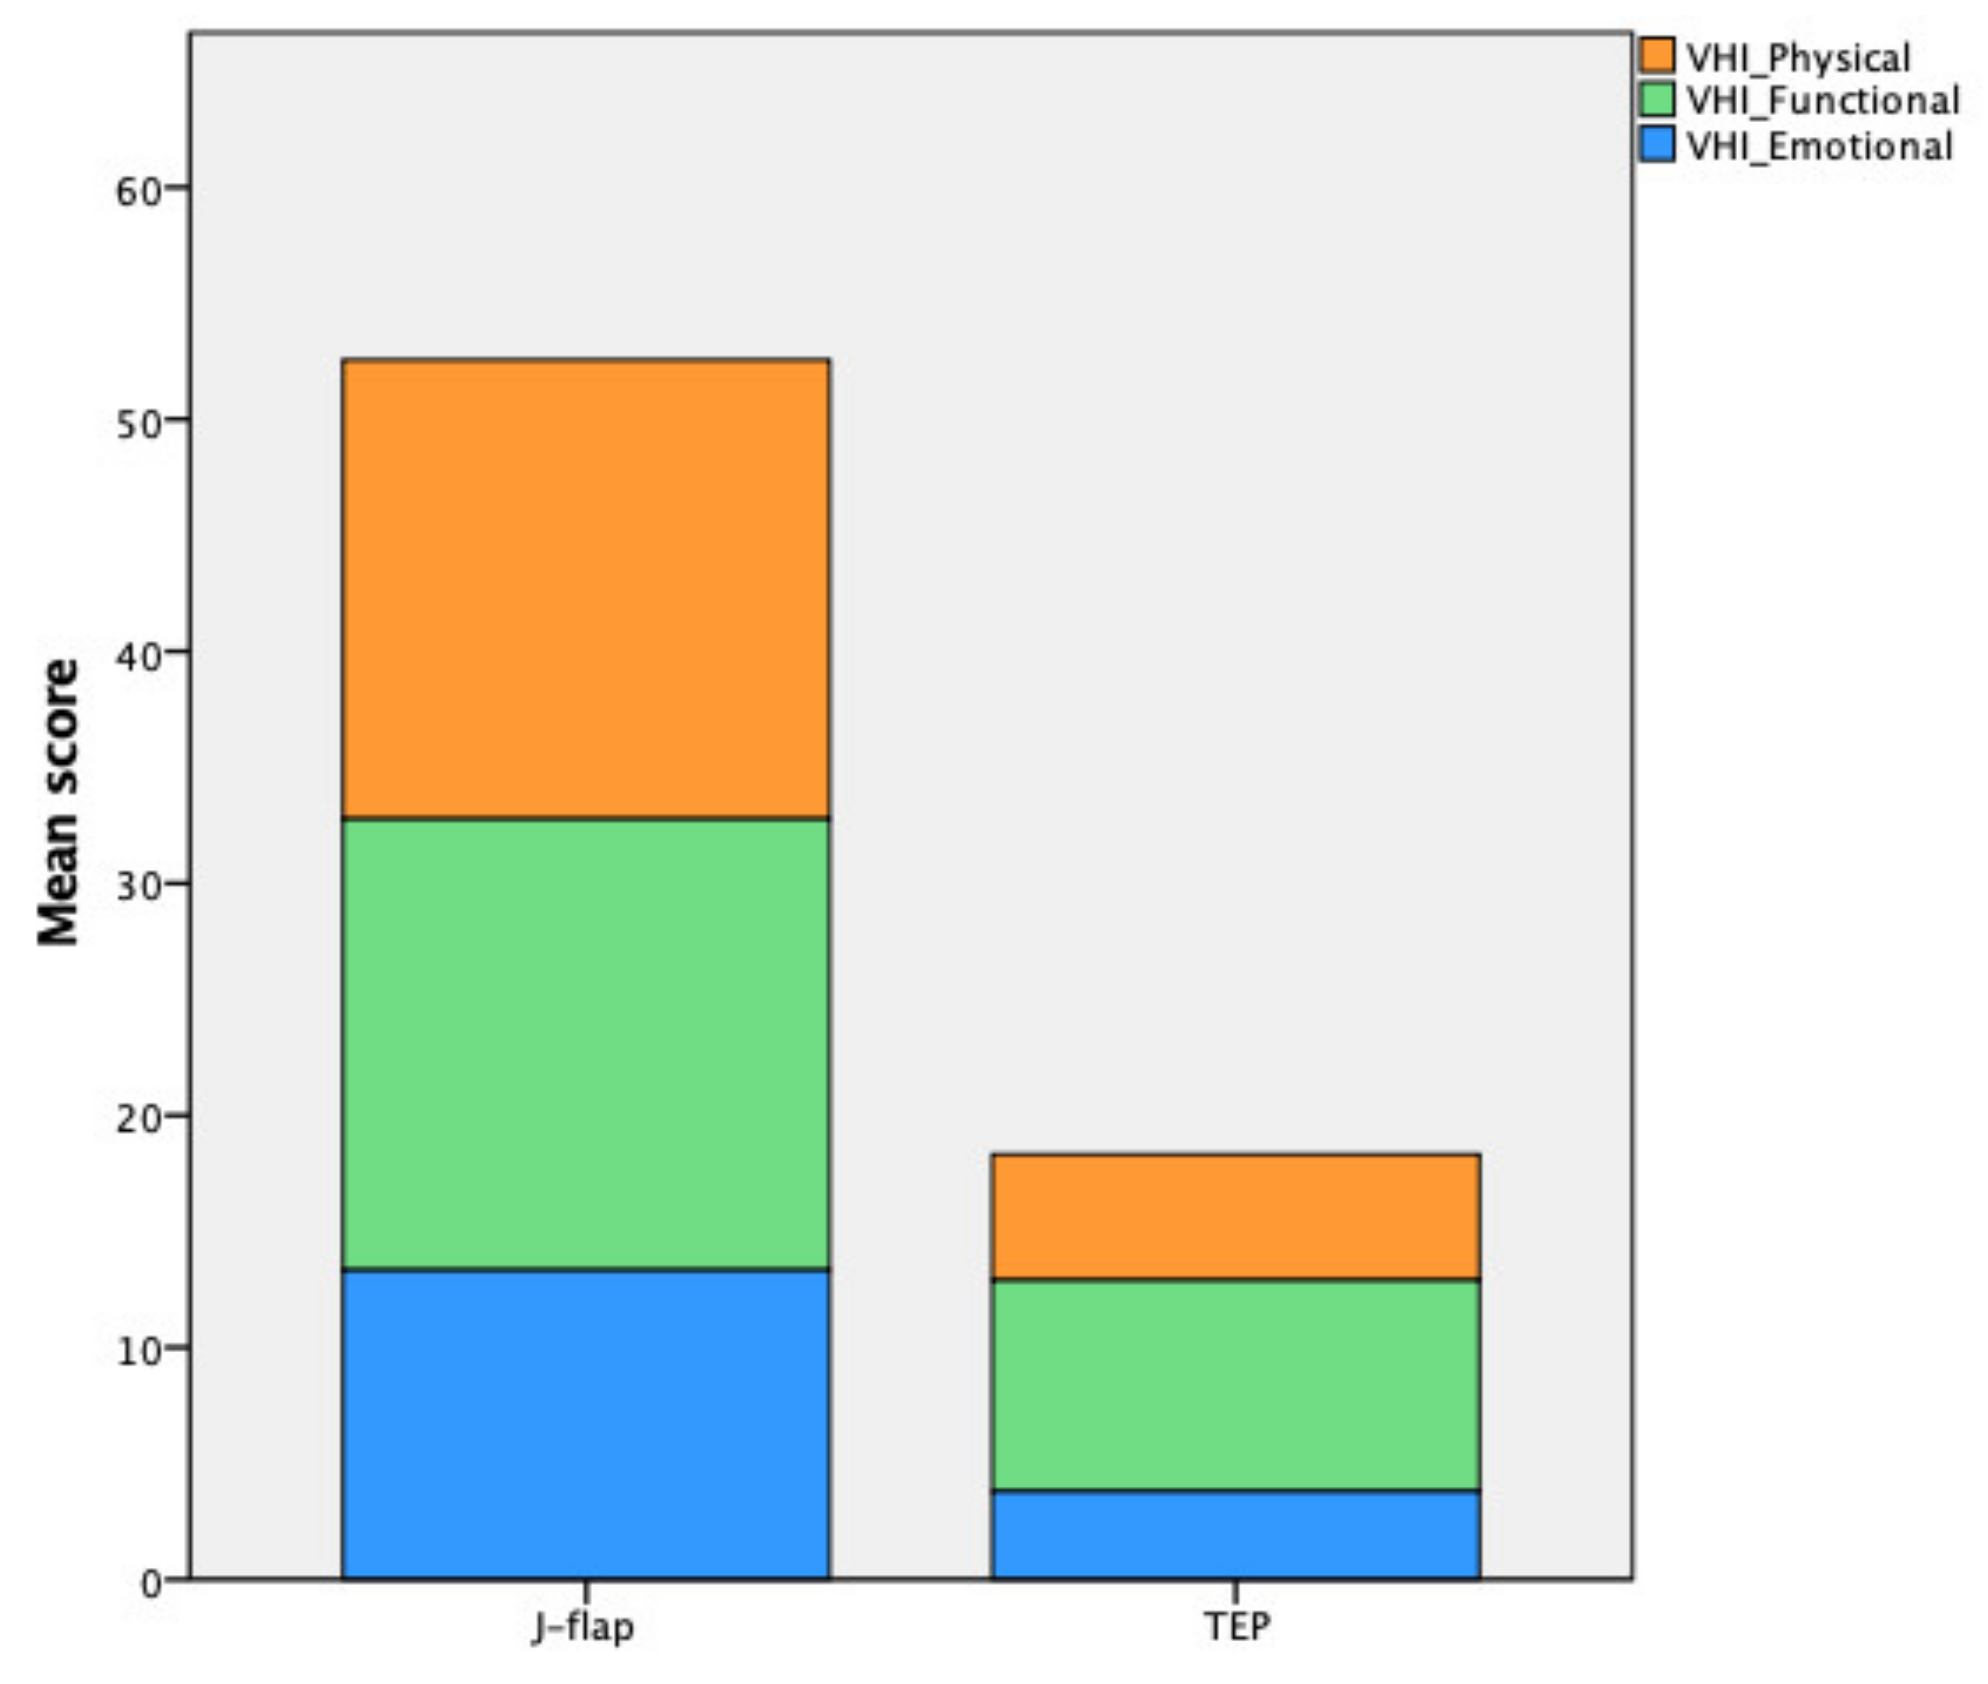

| Voice Handicap Index | J-Flap Group | TEP Group | p-Value |

|---|---|---|---|

| Physical score | 19.78 ± 8.57 | 5.42 ± 3.87 | <0.001 |

| Functional score | 19.44 ± 10.25 | 9.11 ± 6.07 | 0.0001 |

| Emotional score | 13.33 ± 9.74 | 3.79 ± 4.46 | <0.001 |

| VHI total score | 52.56 ± 26.78 | 18.32 ± 11.62 | <0.001 |